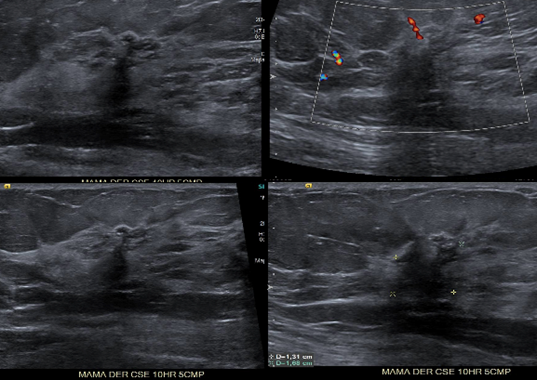

• En Mama DER CSE 10hr 5cmp se visualiza pérdida de la arquitectura del parénquima visualizándose imagen nodular hipoecogenica, irregular, no circunscrita, de contornos mal delimitados, y sombra posterior, con señal periférica al Doppler color, se correlaciona con distorsión visualizada en MX DER CC.

• En la mama derecha en el cuadrante superior externo hora 10 a 5cm de pezón y en correlación con asimetría mamográfica se observa un área nodular mal delimitada e hipoecogénica heterogénea que mide 13 x 15mm

• Área nodular mal delimitada en la mama derecha que se correlaciona con imagen mamográfica y que requiere estudio histológico con Biopsia Core bajo Ultrasonido.

• BIRADS 4C.-